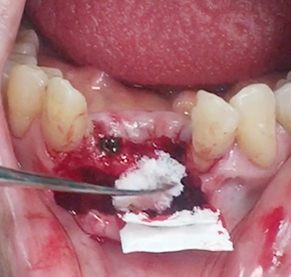

Implants/Bone Grafting

Simultaneous bone graft and implant placement